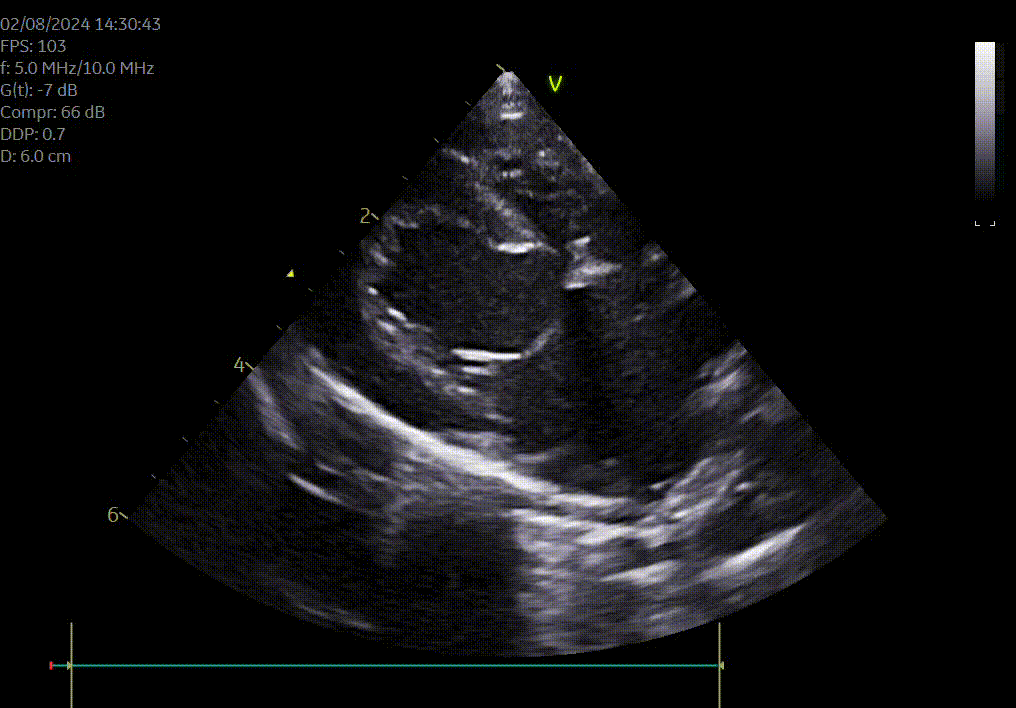

Heeft uw hond of kat een hartruis? Het is dan aangewezen om een echocardiografie (hartfilmpje) uit te laten voeren om na te gaan of er best ondersteunende hartmedicatie moet opgestart worden. Met een echocardiografie gaan we na of het hart normaal gevormd is, normaal werkt en beoordelen we de ergheidsgraad van eventuele kleplekken.

Hartonderzoek - Echocardiografie - Electrocardiografie (EKG) - Radiografie